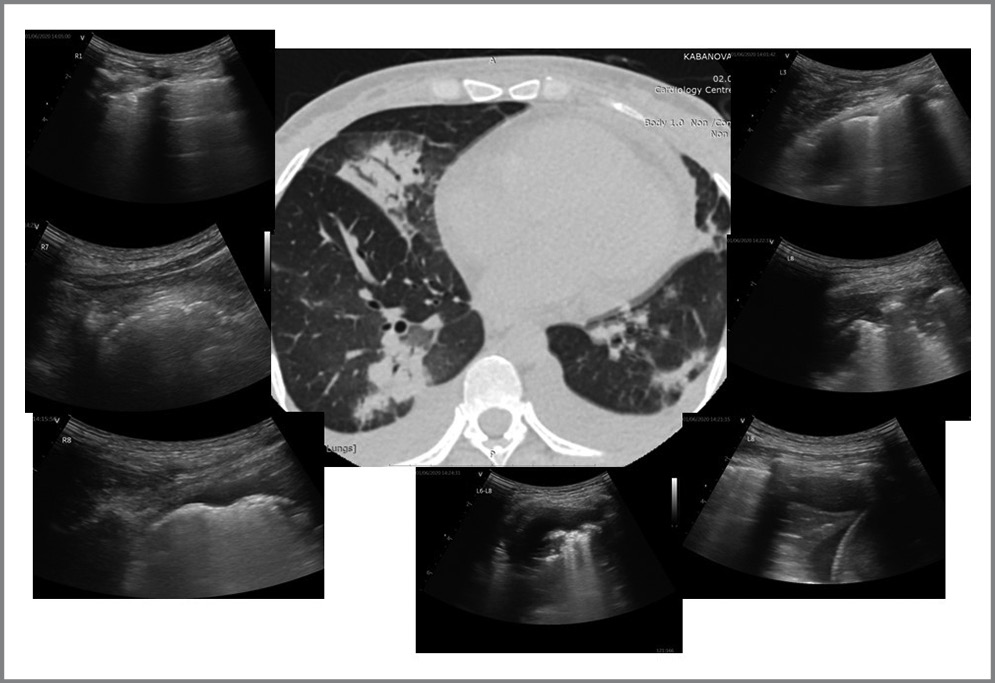

По данным УЗ-протокола у подавляющего большинства (n=33; 91,6%) пациентов прослеживались В-линии. У 26/36 (72,2%) пациентов выявлены патологические изменения в легких в виде участков консолидации (рис. 2). У 6/36 (16,6%) пациентов по данным УЗИ определялись изменения по типу «белое легкое», что соответствовало картине КТ-3–4 (рис. 3). Согласно данным литературы считается, что наличие консолидаций соответствует более тяжелому поражению легких по сравнению с множественными В-линиями [2, 8]. Однако мы, основываясь на собственном опыте, с учетом клинической картины, КТ-диаг- ностики и лабораторных данных отнесли изменения по типу сливных В-линий – «белого легкого» – к наиболее тяжелым поражениям у пациентов с COVID-19. Также к наиболее тяжелому поражению легких можно отнести сочетание отсутствия аэрации («белое легкое») с транслобарными консолидациями и аэробронхограммами.

Рис. 3. УЗИ легких у пациента с COVID-19. На рис. представлены изменения по типу «белое легкое». / Fig. 3. Lung ultrasound in a patient with COVID-19. The figure shows changes of the "white lung" type.

По данным УЗИ легких: при повторном УЗИ легких отмечается положительная динамика – уменьшение распространенности и выраженного инфильтративного поражения легких (рис. 6).

Рис. 6. Сопоставление УЗИ легких с данными КТ согласно разработанному протоколу у пациента с COVID-19 в динамике. / Fig. 6. Comparison of lung ultrasound with CT data according to the developed protocol in a patient with COVID-19 in dynamics.

На КТ органов грудной клетки: двусторонние участки консолидации и интерстициальных изменений в паренхиме легких смешанного характера. Описанные изменения соответствуют среднетяжелой степени поражения (КТ-2); положительная динамика (рис. 6).